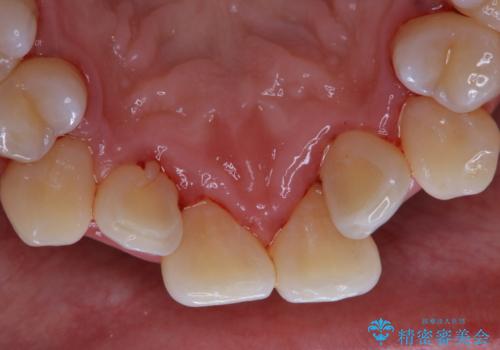

1年ぶりの歯医者でクリーニング

- 忙しく歯科医院でのメンテナンスが1年ぶりとのことで来院されました。PMTC60分コースを行いました。

プラークが放置されると、そこで病原菌が繁殖し始めます。そうなるとバイオフィルム(歯面に強固に付着したばい菌の膜)になり、歯肉に炎症が生じ歯周病の引き金となります。

プラークやバイオフィルムといった細菌などを放置すると歯石となります。歯石になってしまうと歯磨きでは取り除くことができないため、歯科医院にて専門的な機械や材料を使用してクリーニングを受ける必要があります。